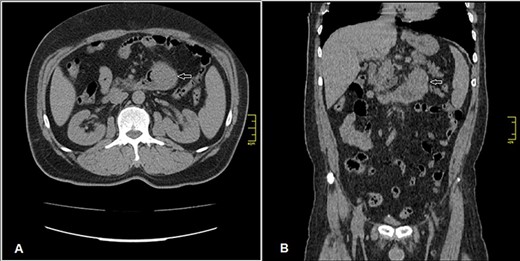

Admission work-up revealed anemia (hemoglobin = 7.8 g/dL, hematocrit = 23%). Emergent upper GI endoscopy showed active bleeding of ulcerated tumor on the third duodenal portion (Fig. 1A and B). Enhanced computed tomography (CT) scan revealed 5 × 4.5 cm hypervascular mass on the previous duodenojejunal anastomosis without metastasis (Fig. 2A and B). Diagnosis of locally recurrent duodenal GIST was suspected. Progressive anemia had developed in spite of transfusion 3 units packed red blood cells, and thus, emergent laparotomy was performed. During laparotomy, we found recurrent mass just on the previous duodenojejunal anastomosis without intraperitoneal or liver implantations (Fig. 3). A careful limited resection of the distal third part of the duodenum with proximal jejunum was carried out (Fig. 4). Side-to-side anastomosis between the second duodenal portion and jejunum was performed (Fig. 5A–C). Feeding jejunostomy tube was inserted. Post-operative course was uneventful. The patient was discharged on the ninth post-operative day. Histopathology report revealed 4 × 3 cm spindle cell type duodenal GIST, mitotic index < 5/50HPF, resection margins free more than 5 mm, intact pseudocapsule with vascular invasion and tumor emboli (Fig. 6A and B). Immunohistochemical staining for CD117 was positive (Fig. 6C). Unfortunately, molecular assessment of the recurrent tumor was unavailable in our institute. Adjuvant imatinib 400 mg/day was administered. To detect any recurrence in the liver or peritoneal cavity during adjuvant imatinib therapy, intensive surveillance with enhanced abdomen and pelvis CT scan every 6 months was recommended [3].

Enhanced CT scan (A) axial section and (B) coronal section: shows well enhanced mass 5 × 4.5 cm (arrow) at previous duodenojejunal anastomosis without intraperitoneal or liver metastasis.